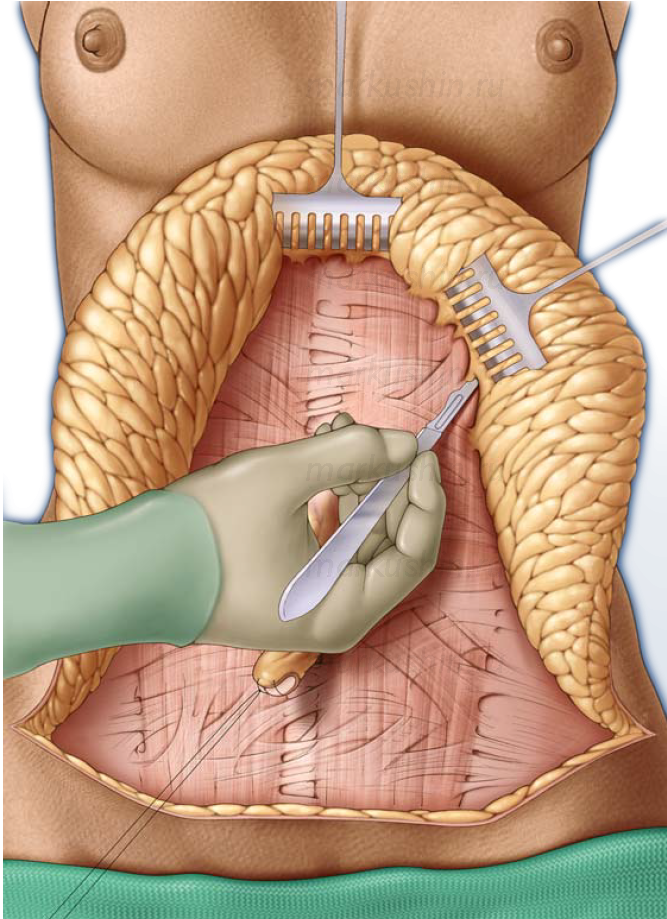

Изображения и визуализация внутренних органов человека

Раздел: Секреты мастерства